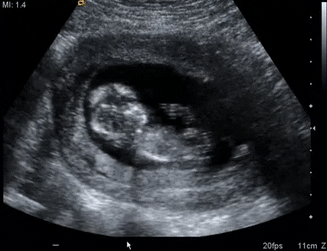

Η αυχενική διαφάνεια (ΑΔ) είναι η υπερηχογραφική εμφάνιση της υποδόριας ποσότητας υγρού πίσω από τον αυχένα του εμβρύου στο πρώτο τρίμηνο της κύησης. Αυξάνεται ανάλογα με το μέγεθος του εμβρύου. Στο 75-80% των εμβρύων με τρισωμία 21 το πάχος της ΑΔ είναι πάνω από την 95η εκατοστιαία θέση για το αντίστοιχο κεφαλοουραίο μήκος του εμβρύου. Το ρινικό οστούν υπάρχει όταν είναι πιο ηχογενές από το υπερκείμενο δέρμα και απουσιάζει αν δε διακρίνεται ή έχει την ίδια ή μικρότερη ηχογένεια από το δέρμα. Το ρινικό οστούν απουσιάζει σε έμβρυα με φυσιολογικό καρυότυπο (ευπλοϊδία) περίπου στο 1-3% ενώ σε έμβρυα με τρισωμία 21 απουσιάζει στο 60%, με τρισωμία 18 στο 50% και τρισωμία 13 στο 40%.

Η προσπάθεια αναγνώρισης των εμβρύων με χρωμοσωμικές ανωμαλίες ξεκίνησε πριν από 40 περίπου χρόνια. Αρχικά βασίστηκε στην ηλικία της μητέρας, πραγματοποιώντας επεμβατικό διαγνωστικό έλεγχο με αμνιοπαρακέντηση σε εγκύους άνω των 35 ετών, βρίσκοντας μόνο το 30% των εμβρύων με σύνδρομο Down. Στο τέλος της δεκαετίας του 1980 προστέθηκε ο έλεγχος βιοχημικών δεικτών ενώ τη δεκαετία του 1990 ξεκίνησε η μέτρηση της αυχενικής διαφάνειας του εμβρύου από τον καθηγητή Κ. Νικολαϊδη. Με την πάροδο των ετών και πολλαπλών ερευνών, σήμερα έχουμε τη δυνατότητα να πραγματοποιούμε τον προγεννητκό έλεγχο χρωμοσωμικών ανωμαλιών από την 11η έως 14η εβδομάδα της κύησης με ποσοστό ανίχνευσης του συνδρόμου Down (Τρισωμία 21) περίπου στο 95%. Αναλυτικότερα, ο έλεγχος του εμβρύου συνίσταται στη μέτρηση της αυχενικής διαφάνειας, την ύπαρξη του ρινικού οστού, την καρδιακή συχνότητα και τη ροή αίματος στο φλεβώδη πόρο και την τριγλώχινα βαλβίδα. Επίσης ελέγχεται η ροή αίματος στις μητριαίες αρτηρίες της μητέρας. Οι υπερηχογραφικές μετρήσεις συνδυάζονται με τις βιοχημικές οι οποίες είναι μέτρηση της πρωτείνης Α (PAPP-A) και ελεύθερης β χοριακής γοναδοτροπίνης (fβ-hCG) στον ορό αίματος της μητέρας.